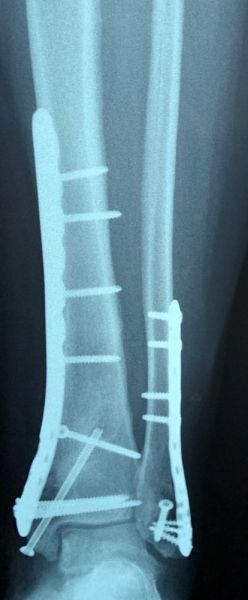

4. Fracture-dislocation of the right ankle in a 50-year-old male.

Treatment: 1st step, external fixation. 2nd step after 14 days, removal the external fixator and at the same time open reduction internal fixation (ORIF)

I. Before surgery, lateral x-ray shows the fracture of tibia and of lateral malleolus II. Post-surgery 1st step, the external fixator III. 2nd step, removal the external fixator and at the same time ORIF